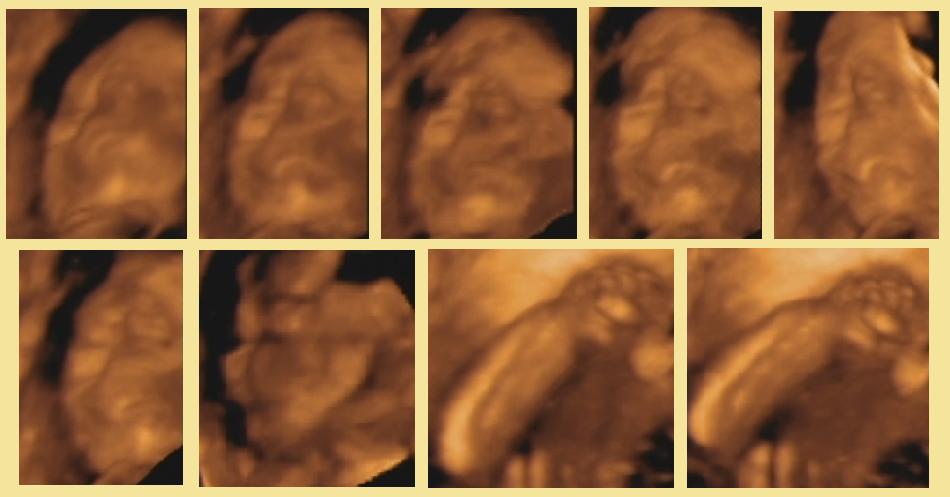

bogini8, wiem ze dla Ciebie obraz z tego skanu jest cenny, ale mnie jakos zdjecia plodu w 3D przerazaja... bez urazy....

pewnie gdybym sama byla na takim skanie i widziala swoje dziecko to patrzyla bym na to inaczej.....